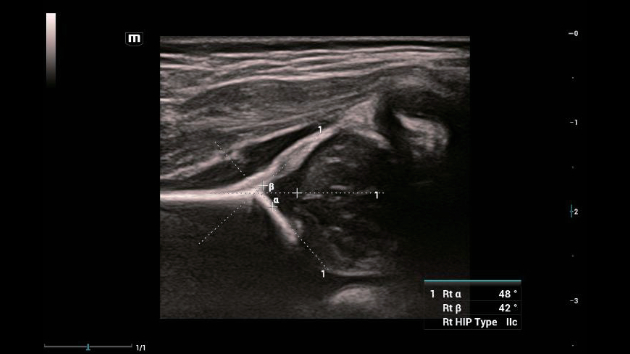

Ongeacht of u werkzaam bent in een ziekenhuis of kliniek, of uw vaardigheden aanscherpt op het gebied van algemene beeldvormingstoepassingen, vrouwengeneeskunde of cardiovasculaire specialismen, in deze serie vindt u zeer krachtige hulpmiddelen waarmee u aan kop kunt blijven.

Uitgebreide?oplossingen voor beeldvorming aangestuurd door ZST?+

Het ZST+?platform is een buitengewone innovatie en revolutie in de wereld van echografie. Het transformeert echografiegegevens van conventionele bundelvorming naar kanaalgegevensverwerking. Het overwint de traditionele afweging tussen ruimtelijke resolutie, temporele resolutie en weefseluniformiteit, en levert een uitzonderlijke beeldkwaliteit voor oneindige beeldvormingsoplossingen met non-stop verbeteringen.